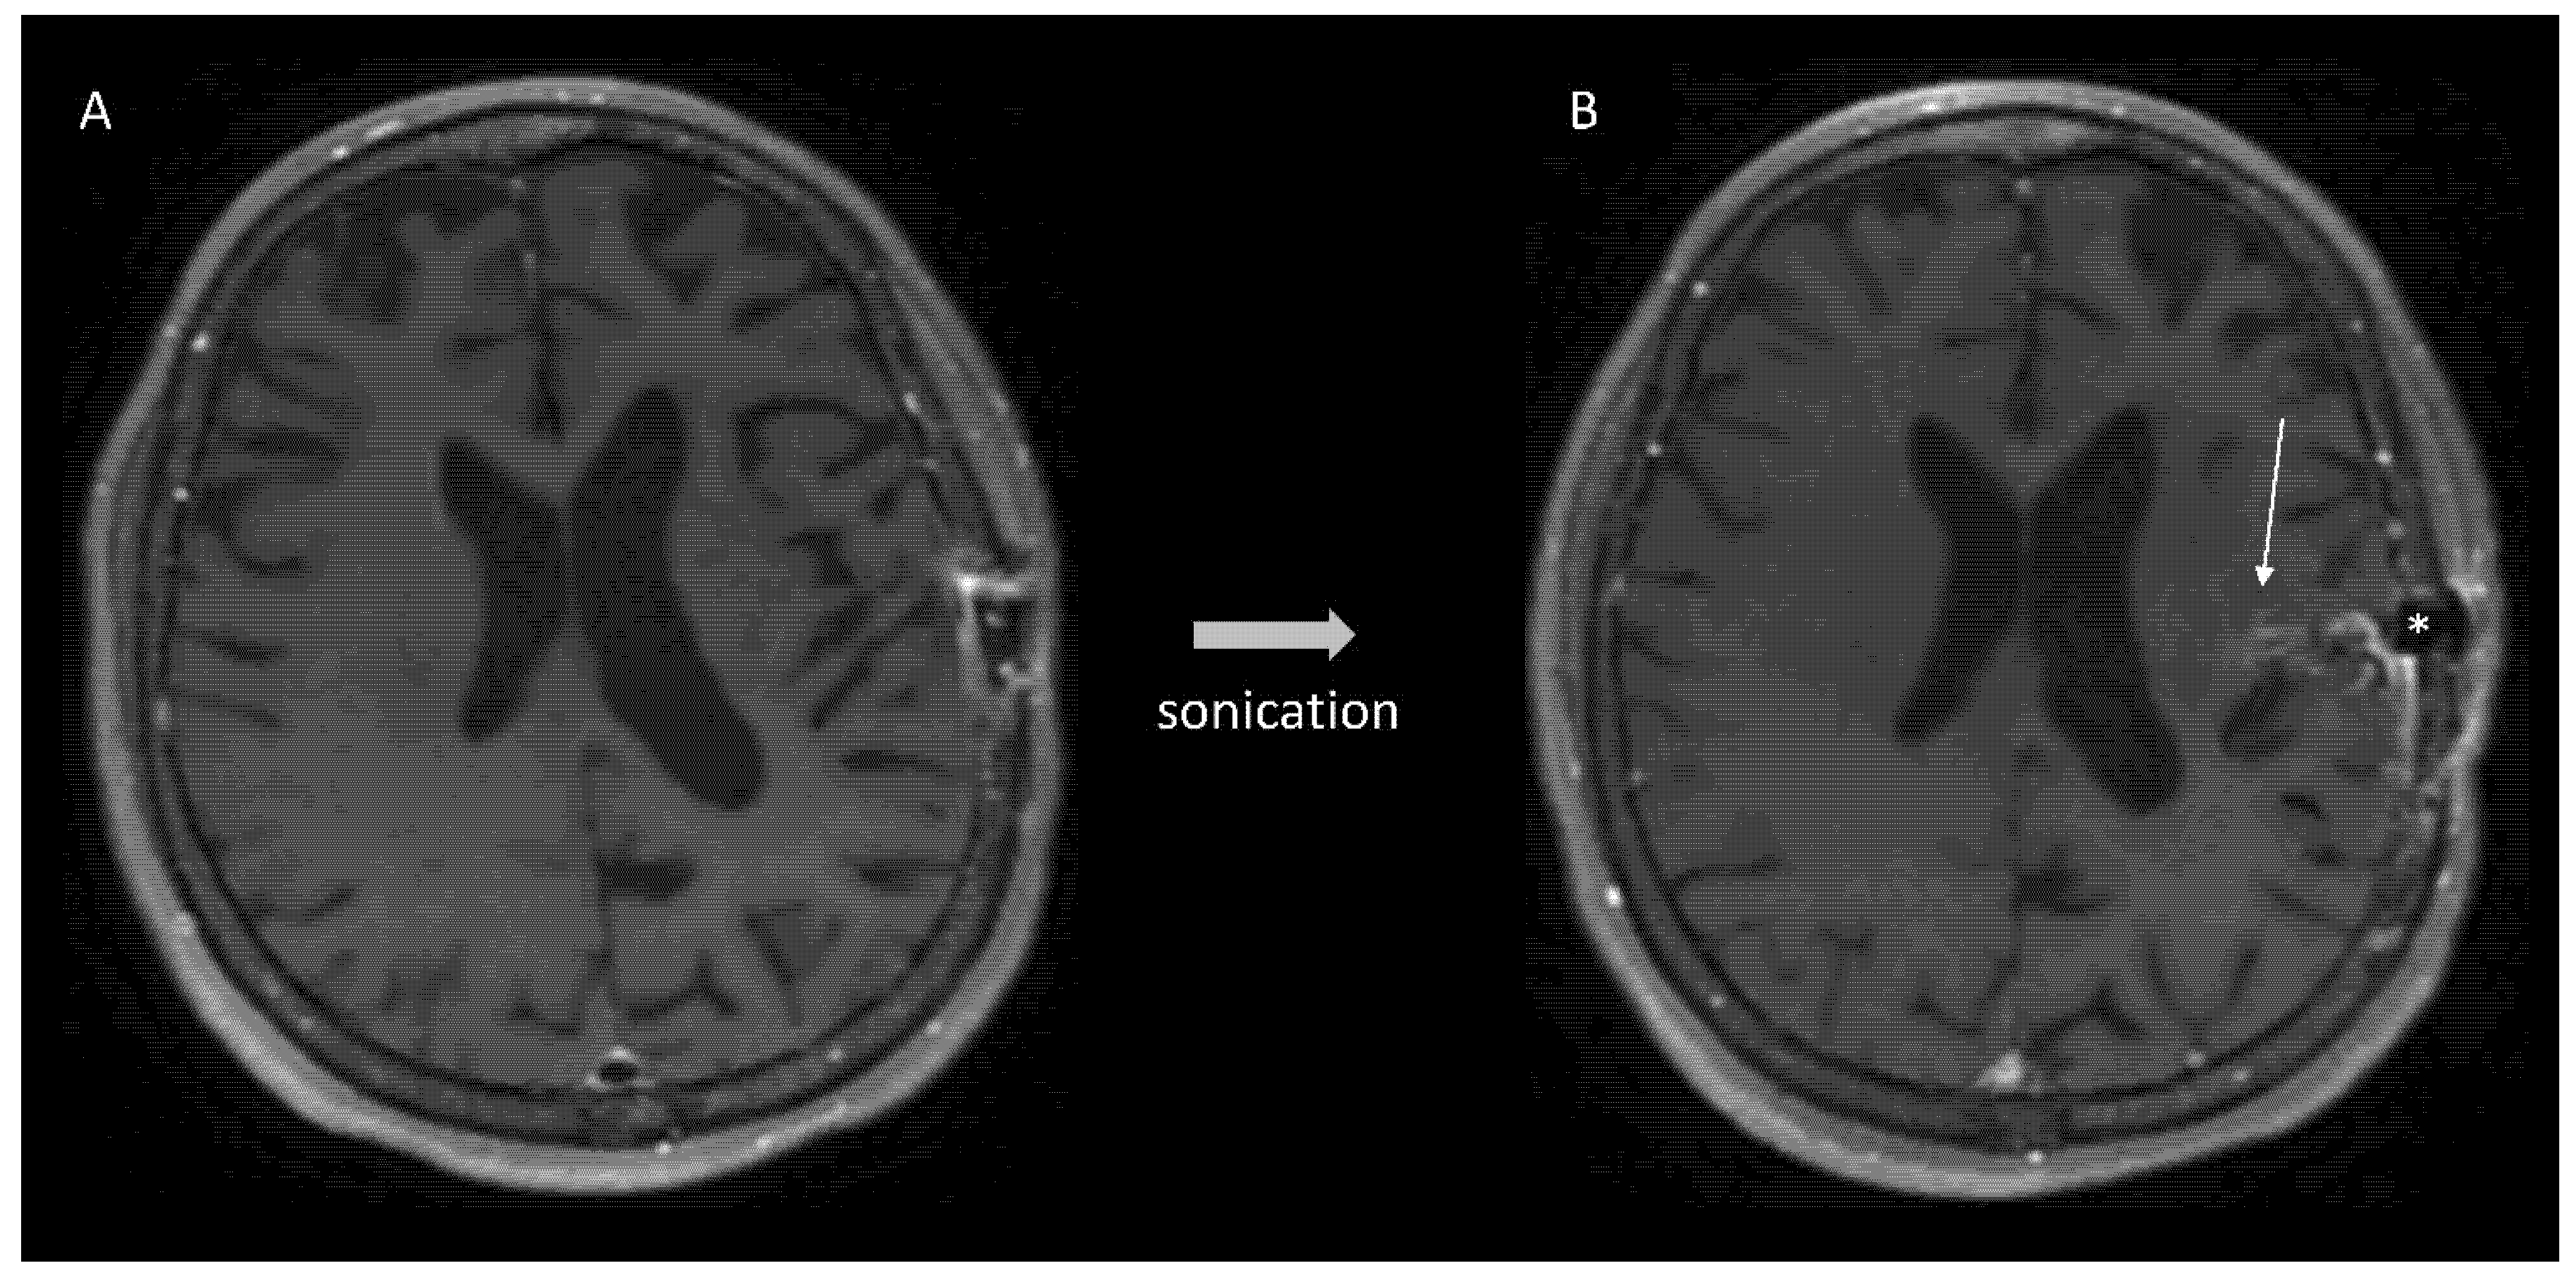

11. Blood–Brain Barrier Disruption by Pulsed Ultrasound

- Idbaih, A.; Canney, M.; Belin, L.; Desseaux, C.; Vignot, A.; Bouchoux, G.; Asquier, N.; Law-Ye, B.; Leclercq, D.; Bissery, A.; et al. Safety and Feasibility of Repeated and Transient Blood-Brain Barrier Disruption by Pulsed Ultrasound in Patients with Recurrent Glioblastoma. Clin. Cancer Res. 2019, 25, 3793–3801. [Google Scholar] [CrossRef] [Green Version]

- Carpentier, A.; Canney, M.; Vignot, A.; Reina, V.; Beccaria, K.; Horodyckid, C.; Karachi, C.; Leclercq, D.; Lafon, C.; Chapelon, J.-Y.; et al. Clinical Trial of Blood-Brain Barrier Disruption by Pulsed Ultrasound. Sci. Transl. Med. 2016, 8, 343re2. [Google Scholar] [CrossRef] [PubMed]

- Horodyckid, C.; Canney, M.; Vignot, A.; Boisgard, R.; Drier, A.; Huberfeld, G.; François, C.; Prigent, A.; Santin, M.D.; Adam, C.; et al. Safe Long-Term Repeated Disruption of the Blood-Brain Barrier Using an Implantable Ultrasound Device: A Multiparametric Study in a Primate Model. J. Neurosurg. 2017, 126, 1351–1361. [Google Scholar] [CrossRef] [PubMed] [Green Version]